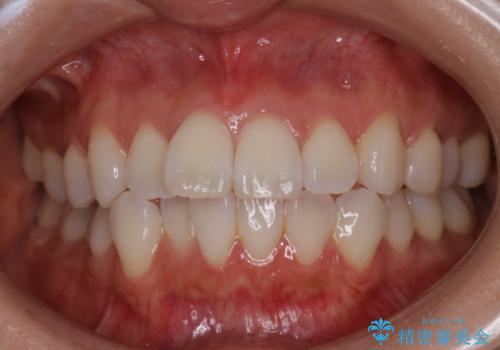

[マウスピース矯正] がたがたの歯並びをきれいにしたい

![[マウスピース矯正] がたがたの歯並びをきれいにしたいの症例 治療前](https://seimitsushinbi.jp/wp/wp-content/uploads/2025/06/0d238550c8a0fddc4de7b2c337c6c786-500x350.jpg?v=1750323380)

![[マウスピース矯正] がたがたの歯並びをきれいにしたいの症例 治療後](https://seimitsushinbi.jp/wp/wp-content/uploads/2025/06/IMG_0002-2-500x350.jpg?v=1750323305)